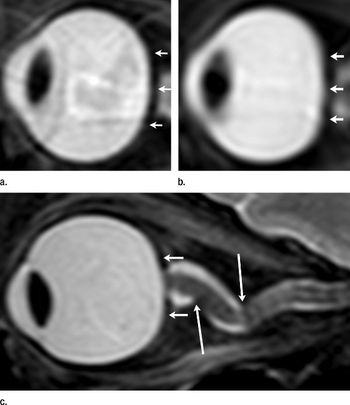

MRI findings show that astronauts exposed to zero gravity for prolonged periods can develop brain and eye abnormalities.